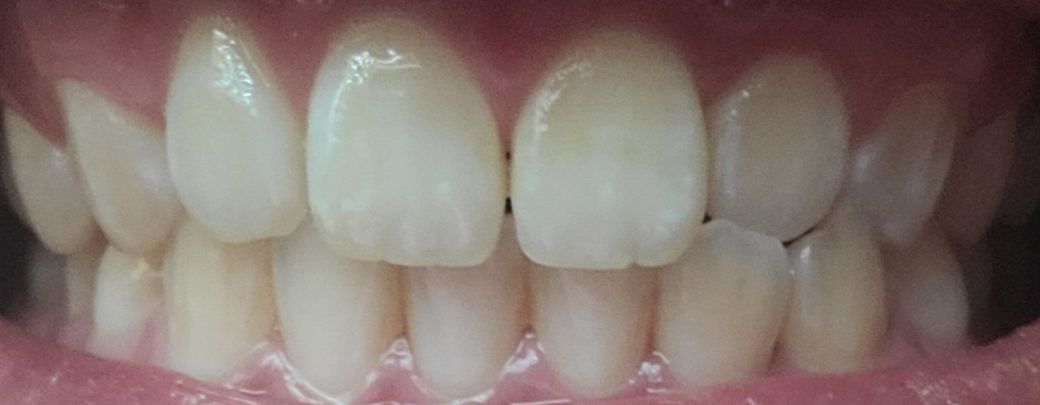

비발치 교정 중 인비절라인과 자기결찰장치 중에 고민중 입니다(앞니 살짝벌어짐,오른쪽 송곳니쪽 반대교합, 약간의 돌출입)

인비절라인과 클리피씨로 치아전체 교정 및 사랑니공간으로 치아전체후방 이동 시 결과 및 교정과정 면(고통, 교정기간, 만족도)에서 어느것이 나을까요?

(치과의사쌤이 치열이 전체적으로 좋고 앞니치근이 짧아 발치는 비추천하셨고 후방이동도 비발치라 큰차이는 없겠지만 최대한 해보겠다고 하셨고 인비절라인또는 결찰장치 비발치 전체교정또는 부분교정 이렇게 3가지 추천해주셨습니다)

• 2번 째 사진

솔직히 말씀드리면 교정을 권해드리지 않습니다. 지금 상태에서 교정을 하더라도 말씀하신 것들을 개선시키기 어렵고 지금도 치열 및 교합이 훌륭한 편입니다. 치열을 전반적으로 뒤로 미는 것은 교정에서 매우 어려운 것입니다. 지금 교합 자체가 나쁘지 않으며 어떤 교정을 하더라도 교정 전후의 큰 차이가 없을 것으로 보입니다. 따라서 권해드리지 않습니다.

크게 치열에 문제가 없으시다면 인비절라인 클리피씨등 어떤걸 하셔도 효과는 비슷할것같습니다. 물론 비용적인 부준에서 차이가 나겟지만 결과는 크게 차이가 없을것같습니다